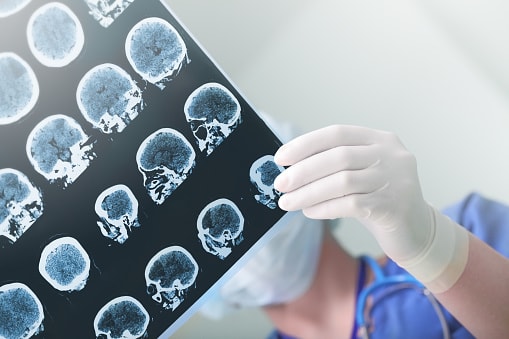

You’re often advised to lower your cholesterol levels because it can result in a heart-related complication. But studies have revealed that having high cholesterol may contribute to a higher Alzheimer’s disease risk. The findings were published in Nature Chemistry and they describe how cholesterol in the brain may act as a trigger for toxic clusters ...click here to read more